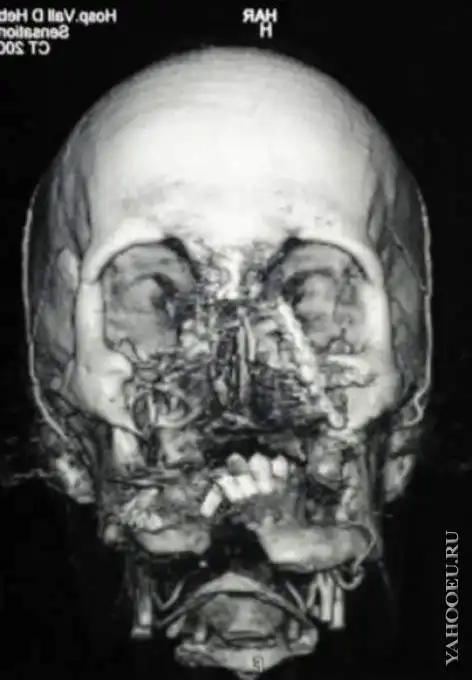

Результат пересадки лица!

"До" на снимках......

это "до"? это, наверно, уже "после", лицо, видимо, совесм снесло и был лишь череп?

Не наверное, а так и есть, на рентген посмотрите (6-е фото), несчастному половину лица раскрошило.

На шестой фотографии сверху смотрите как было до операции

судя по рентгену "до", поциент- неудавшийся самоубийца, приставивший бердан к подбородку и снесший себе лицо.

фотки все "после"- нижняя часть лица заметно отличается от верхней и, судя по обвисшей челюсти, он эту часть вообще не контролирует.

Это наследственное заболевание связано с развитием опухолей периферических нервов - нейрофибром, и часто приводит к обезображивающим изменениям внешности. 30-часовая операция была проведена 26-27 января в севильской клинике Вирген дель Росио, в ней участвовали более ста сотрудников различных отделений клиники Пациент по-прежнему с трудом может говорить, однако на пресс-конференции он первым делом поблагодарил команду хирургов. "Я счастлив и хотел бы поблагодарить семью донора и команду медиков", - сказал Рафаэль. Впереди еще месяцы реабилитации, но медики уже с оптимизмом говорят о результатах. "Пациент может чувствовать прикосновения к губам и щекам. Лицо также чувствительно к теплу и холоду. Он даже смог побриться", - сказал глава отделения лицевой хирургии Хуан Давид Гонсалес Падилла. По словам директора отделения пластической хирургии клиники Вирген дель Росио Томаса Гомеза Сиа, хирурги довольны результатами операции: после пересадки донорских тканей лицо мужчины приобрело те черты, которые имело до развития обезображивающего заболевания. "Больной узнал себя после операции, это подтверждает и он сам, и его родственники", - сообщил Сиа. Рафаэлю по-прежнему трудно говорить, и, по словам медиков, он вряд ли восстановит полный контроль над своим языком в ближайшие три месяца. Его лицо тоже еще воспалено. Рафаэль появился на пресс-конференции вместе со своей матерью и сестрой. Он попросил журналистов беречь его право на личную жизнь и после этой пресс-конференции не преследовать ни его, ни его родственников. 34-летний Рафаэль стал третьим человеком в Испании и десятым в мире, кому была сделана операция по частичной пересадке лица. Всего в мире известно об 11 операциях по частичной трансплантации лица. А в апреле испанские врачи впервые полностью пересадили его пациенту. Операция прошла в барселонской клинике "Вал д'Эброн" и длилась 24 часа. В ней участвовало более 30 специалистов. Кандидатом на пересадку стал 30-летний мужчина, чье имя не разглашается. Известно лишь то, что пять лет назад он случайно выстрелил себе в лицо из ружья, буквально снеся большую часть лица, включая нос и подбородок. В результате мужчина все это время не мог нормально есть, глотать, говорить и даже дышать. Попытки восстановить лицо оканчивались ничем. Теперь же благодаря испанским специалистам он, наконец, получил новые лицевые мышцы, кожу, нос, губы, челюсть, зубы и скулы. Донором для операции стал человек, погибший в автокатастрофе. Однако врачи подчеркивают, что новое лицо не будет походить ни на донора, ни на прежний облик пациента – получится некий гибрид. После операции у мужчины остались лишь два незаметных шрама на лбу и шее.